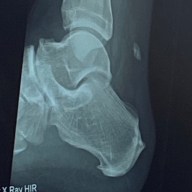

My Achilles injury

A blog documenting my journey through recovery of a ruptured Achilles Tendon